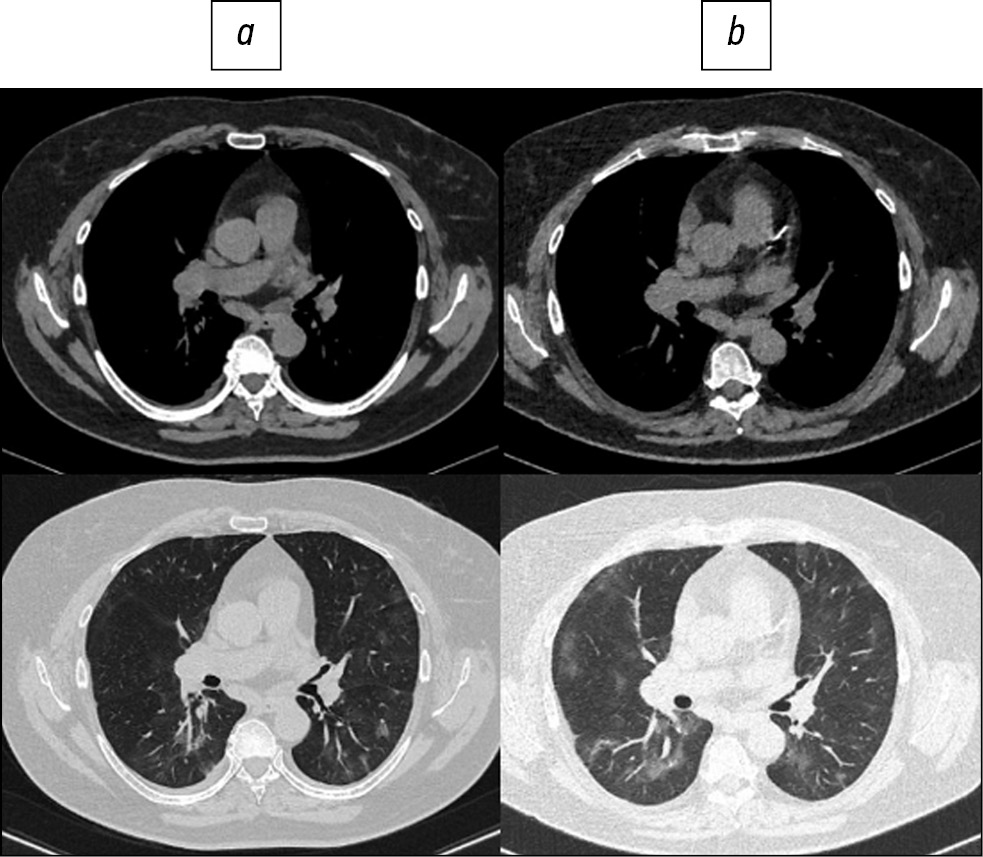

Fig. 2. Patient, 72 years old: standard computed tomography at admission was performed with radiation exposure of 2.1 mSv (a), low-dose computed tomography - 0.87 mSv (b).

Fig. 3. Patient, 60 years old: standard computed tomography at admission was performed with a radiation load of 3.3 mSv (a), low-dose computed tomography - 1.1 mSv (b).

Here are illustrative examples of clinical cases (Figs. 1–6), demonstrating the similarity of diagnostic value of two aforementioned research methods. Columns on the left (a) show images of a standard CT scan performed upon admission of the patient to the hospital, and columns on the right (b) present LDCT over time. The top line of images indicates the pulmonary window mode, whereas the bottom line indicates the mediastinal window mode. For comparison, values of radiation exposure in each case are presented. Time intervals between standard CT and LDCT were 2–7 days; thus, the primary endpoint was reached in all patients enrolled in the study.